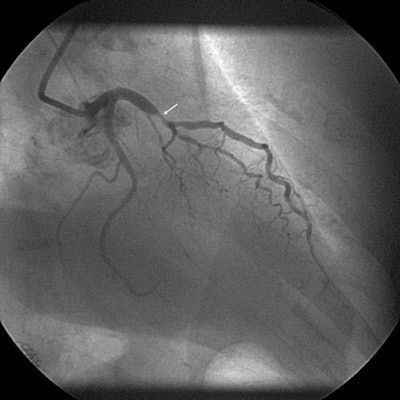

Significant coronary stenosis of left anterior descending branch is shown in the same patient, a 53-year-old man, using CCTA (above) and invasive coronary angiography (below). Images courtesy of Dr. Maciej Krupinski.